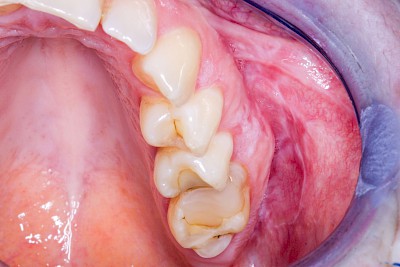

Bei der sogenannten Leukoplakie handelt es sich um eine Hyperkeratose (Hornhautbildung), die auch entarten kann (fakultative Präkanzerose).

Nach dem Erscheinungsbild werden verschiede Typen unterschieden:

- Plan (Leukoplakia simplex bzw. plana): homogen-weiß, meist klar begrenzt, Oberfläche glatt. Entartungsrisiko 0–3 %

Neben mechanischen Reizen zählen auch Rauchen und Alkoholkonsum zu den möglichen Ursachen. Manchmal sind diese Veränderungen, etwa wenn die Auffälligkeit im Bereich der Wange oder auch der Zunge auf Höhe der Zahnreihe im Zubiss (Okklusionsebene) zu liegen kommt, auch auf Wangen- bzw. Zungenkauen als Ursache zurückzuführen. Die beobachtbaren Veränderungen reichen hier von diskreten homogen-weißlichen Strichen (Linea alba) bis hin zu erosiv "unruhigen" Schleimhautarealen. Je nachdem, wie intensiv und wie ausdauernd und mit welcher Kraft diese Habits ausgeführt werden. Auch hier sollte auf eine Verhaltensänderung hingewirkt und ein Zahnarzt verständigt werden.